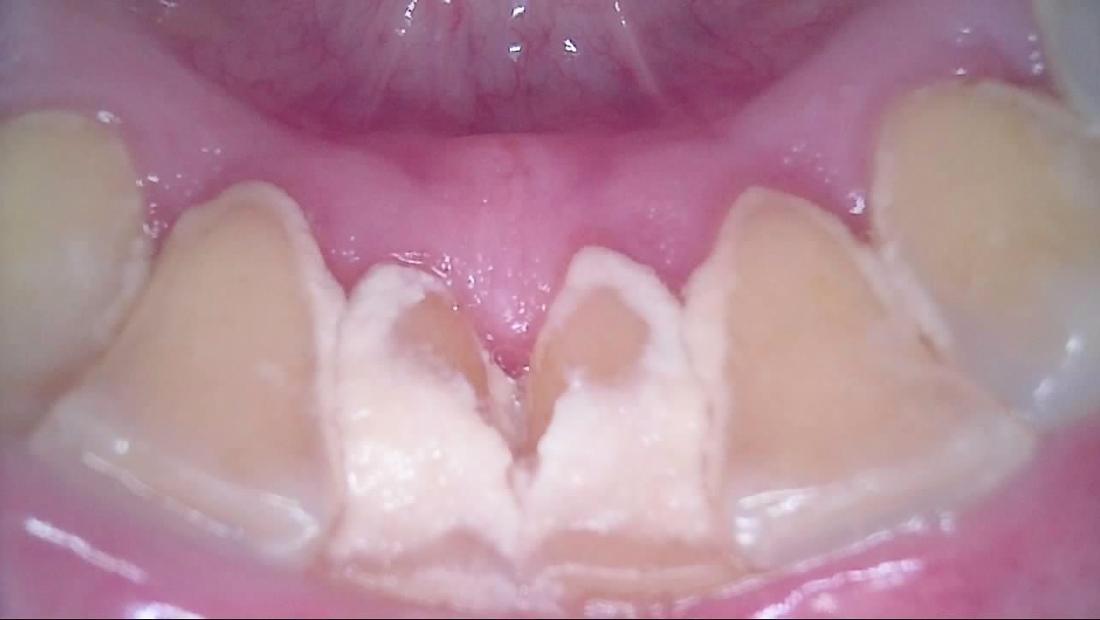

When we clean your teeth, we are removing buildups of calculus.tartar as well as buildups of plaque bacteria on your teeth. Here is a before an after example of a cleaning taken ten minutes apart. After a cleaning, your gum tissues are ready for your home care to help them to become much healthier in the future.